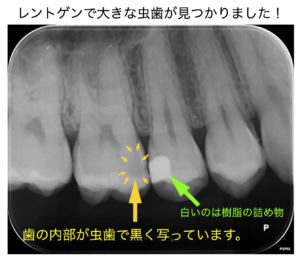

| 治療内容 | 口腔内審査を行ったところ、右上の歯と歯の間に虫歯を発見した。虫歯は大きく広がっており、インレー修復が必要となった。材料は金属かセラミックかを選択できるが、虫歯の再発をなるべく抑えるために、セラミックによる治療を選択された。 1回目に、虫歯の除去、仮詰めを実施。2回目にデジタル印象(型取り)を行い、3回目にセラミックインレーを装着。嘔吐反射が強いが、デジタル印象なので、全く問題なく型取りが可能であった。 |